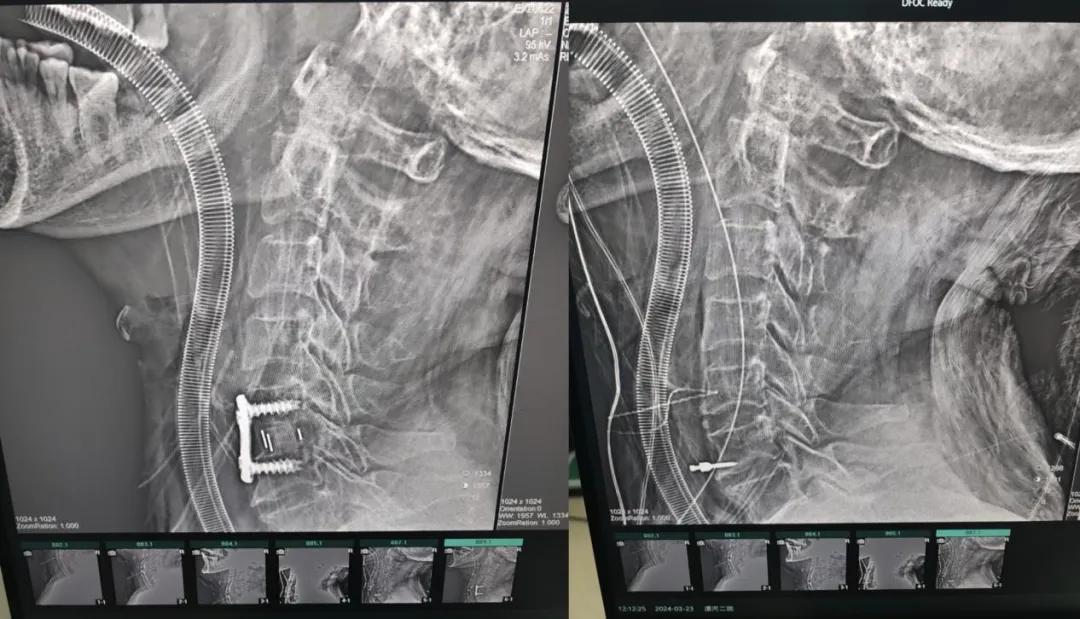

近日,70歲的馬阿姨,因摔傷后出現(xiàn)持續(xù)性頸部疼痛伴右側(cè)肢體無力、麻痛,影響日常生活。于是來到市二院神經(jīng)外科就診,經(jīng)檢查發(fā)現(xiàn):頸椎MR示:頸3/4、4/5、5/6、6/7椎間盤變性突出(中央型)并繼發(fā)性椎管變窄,頸椎退行性改變,頸5椎體水平頸髓水腫。神經(jīng)外科副主任劉沛濤根據(jù)患者癥狀、體征、影像學三者結(jié)合診斷為“脊髓型頸椎病”,考慮到患者癥狀逐漸加重、保守治療效果不佳等情況,建議盡快手術(shù)治療。

經(jīng)過縝密的術(shù)前準備和手術(shù)計劃,在鄭大一附院神經(jīng)外科張風江教授的指導下,神經(jīng)外科團隊順利為患者實施“顯微鏡下頸椎前路C5/C6椎間盤切除椎間融合+內(nèi)固定術(shù)”,手術(shù)時間不到1小時。術(shù)后患者恢復情況良好。